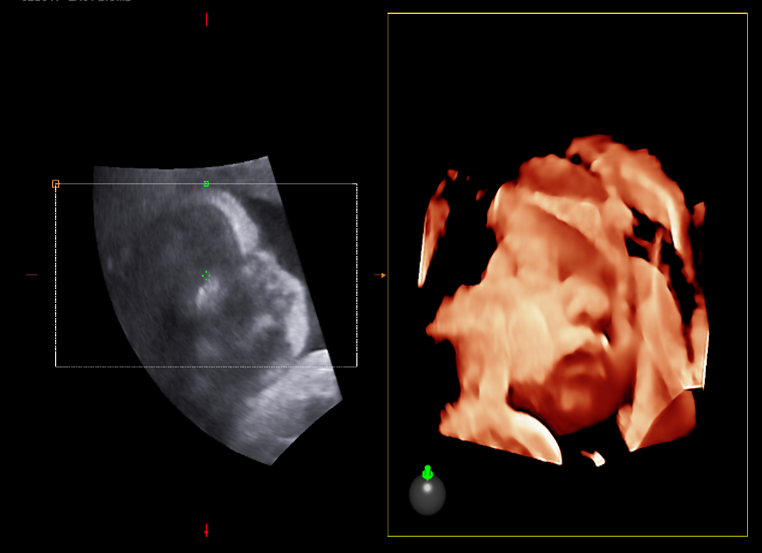

X-light – Professional 3D/4D ultrasound technology, integrated virtual light source and able to re-generate the fetal face, enhance clinical confidence and promote maternal-fetal bonding